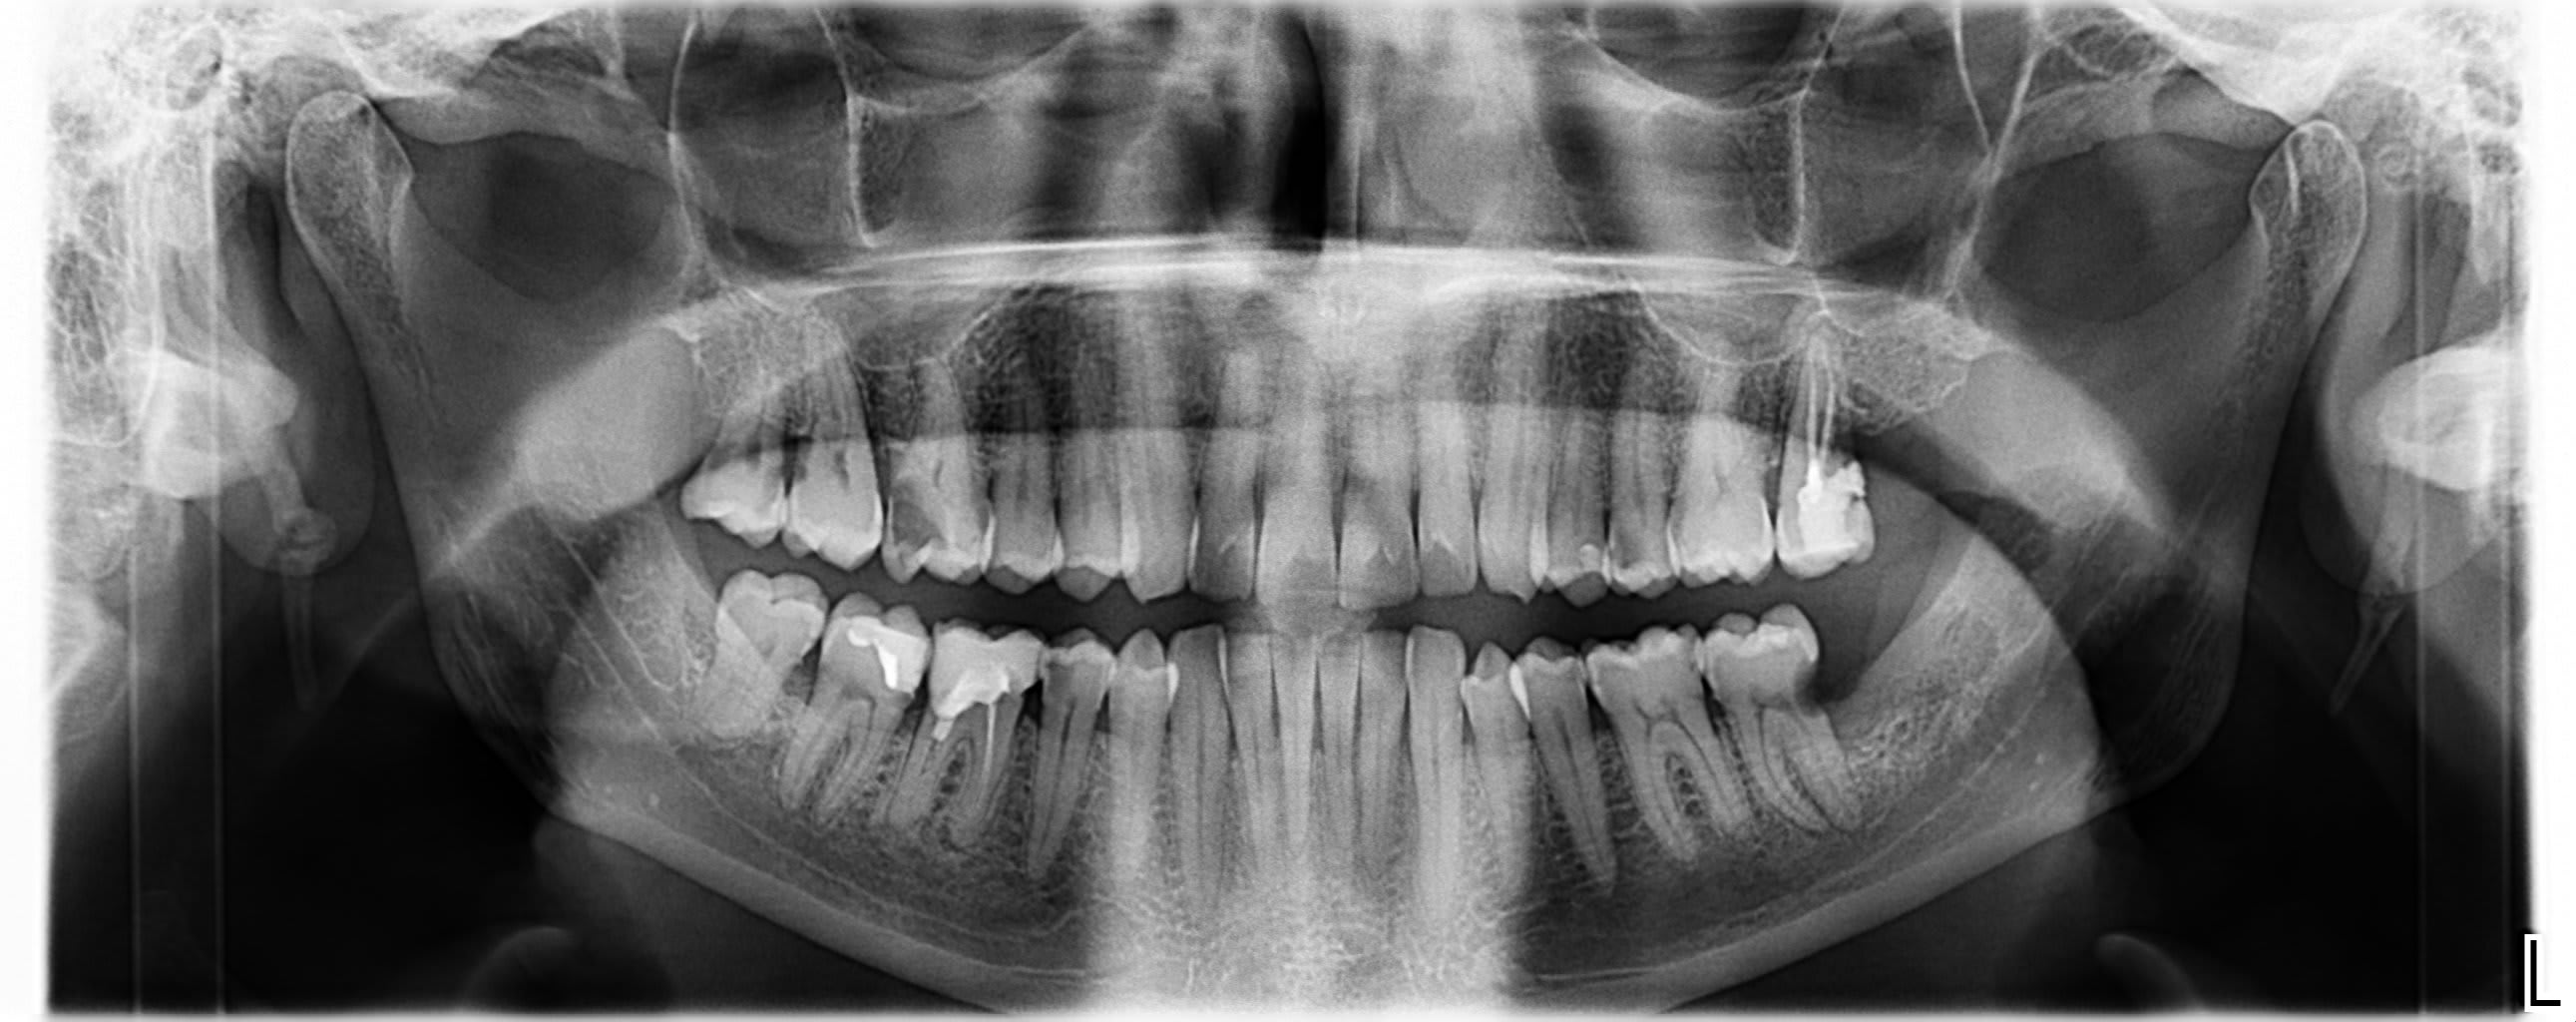

j'ai un patient (50ans) très sympa (et solvable!) de passage chez moi et qui est de Chambery

Son praticien semble passer à coté des choses...

Je l'ai mis au courant de ses multiples problèmes